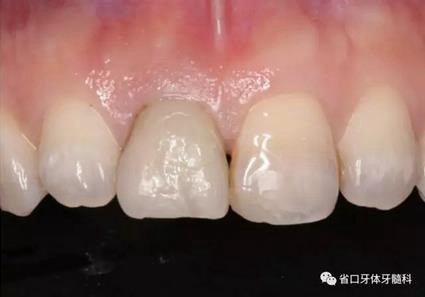

圖1 術(shù)前口內(nèi)照

圖2 術(shù)前口內(nèi)照

圖3 術(shù)前口內(nèi)照